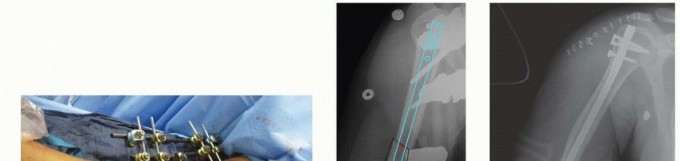

r DEFINITION Incidence: 3% to 5% of all fractures 12 The AO/ASIF classification of humeral shaft fractures is…